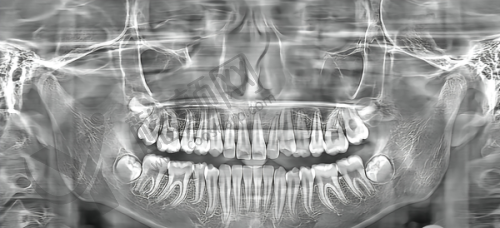

肖步挺种植牙实例

曾有一位老年患者,全口牙齿缺失多年,生活受到了极大的影响,饮食只能选择软烂的食物,营养摄入不足。肖步挺院长为其进行了详细的口腔检查和评估后,制定了全口无牙颌种植修复方案。在手术过程中,肖院长凭借不错的技术和丰富的经验,顺利完成了种植手术。术后,患者修复良好,重新拥有了健康的牙齿,能够正常饮食,生活质量得到了极大的提升。患者对肖院长的技术和服务非常满意,称赞他是一位医术高超、职责心强的好医生。